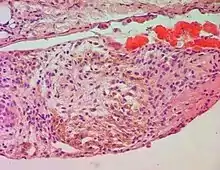

A siderophage is a hemosiderin-containing macrophage. Heart failure cells are siderophages generated in the alveoli of the lungs of people with left heart failure or chronic pulmonary edema, when the high pulmonary blood pressure causes red blood cells to pass through the vascular wall.[1] Siderophages are not specific of heart failure. They are present wherever red blood cells encounter macrophages, such as pulmonary hemorrhage.

In left heart failure, the left ventricle can not keep pace with the incoming blood from the pulmonary veins. The resulting backup causes increased pressure on the alveolar capillaries, and red blood cells leak out. Alveolar macrophages (dust cells) engulf the red blood cells, and become engorged with brownish hemosiderin.

In chronic pulmonary edema, alveolar septa become thick and fibrous, again increasing pressure on alveolar capillaries and resulting in leakage of red blood cells which undergo phagocytosis by alveolar macrophages.